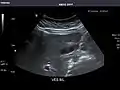

Liver

Ultrasonography of the liver with some standard measurements[6]

In patients with deranged liver function tests, ultrasound may show increased liver size (hepatomegaly), increased reflectiveness (which might, for example, indicate cholestasis), gallbladder or bile duct diseases, or a tumor in the liver.

Ultrasonography of liver tumors involves two stages: detection and characterization. Tumor detection is based on the performance of the method and should include morphometric information (three axes dimensions, volume) and topographic information (number, location specifying liver segment and lobe/lobes). The specification of these data is important for staging liver tumors and prognosis. Tumor characterization is a complex process based on a sum of criteria leading towards tumor nature definition. Often, other diagnostic procedures, especially interventional ones, are no longer necessary. Tumor characterization using the ultrasound method will be based on the following elements: consistency (solid, liquid, mixed), echogenicity, structure appearance (homogeneous or heterogeneous), delineation from adjacent liver parenchyma (capsular, imprecise), elasticity, posterior acoustic enhancement effect, the relation with neighboring organs or structures (displacement, invasion), vasculature (presence and characteristics on Doppler ultrasonography and contrast-enhanced ultrasound (CEUS).